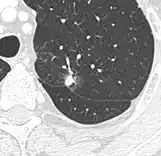

Lung nodule abutting a pulmonary cyst.[9]

• A lung nodule abutting a pulmonary cyst is a rare finding, yet indicating cancer.[9]